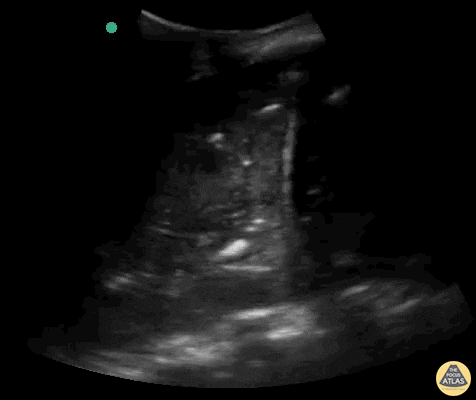

Lignes B pathologiques. Ce GIF montre la présence de nombreuses lignes B (plus de 3 par espace intercostal). Ces artéfacts verticaux, "en queue de comète", partent de la ligne pleurale et s'étendent jusqu'au bas de l'écran sans s'atténuer, effaçant les lignes A. Ils signent une perte d'aération pulmonaire